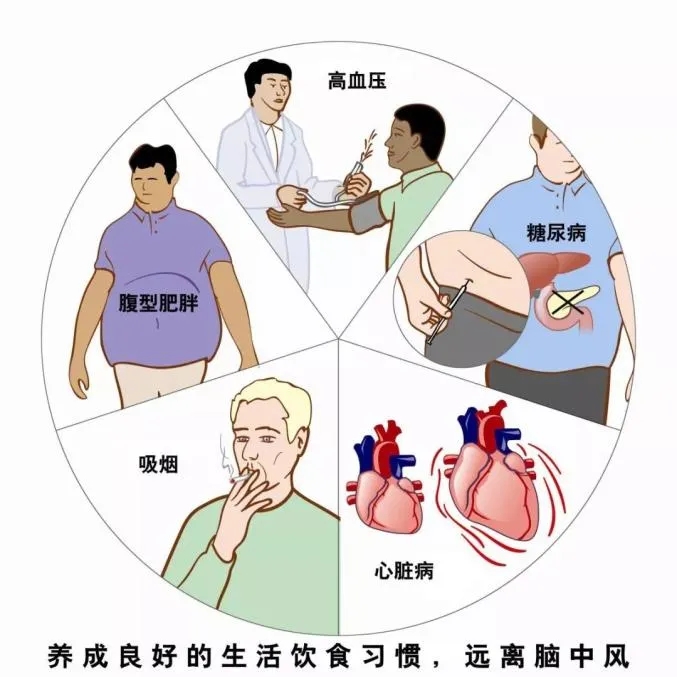

相关疾病患者注意以下5点

1、高血压患者,应注意控制高血压;

2、高血脂症患者,应注意控制血脂;

3、糖尿病患者应积极控制血糖;

4、房颤或有其他心脏疾病患者,应控制心脏病相关危险因素。

5、有以上疾病的患者,应定期到医院复诊。